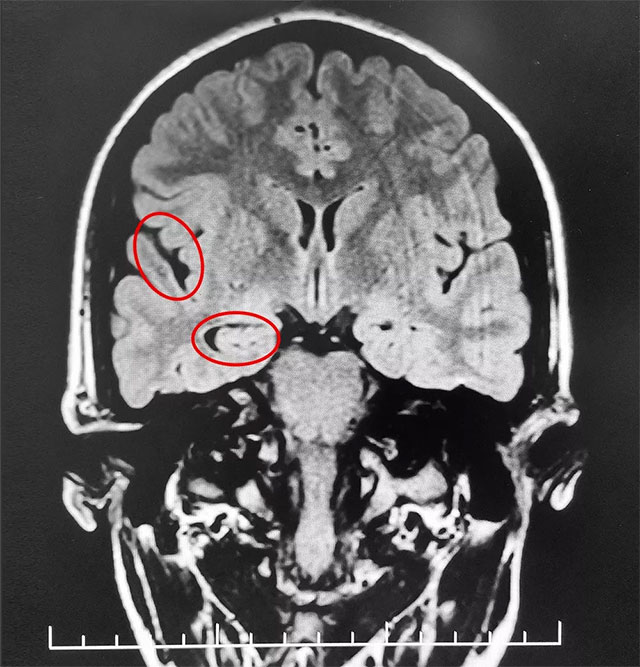

▲ 通过系列检查最终明确患者致癫灶

经磁共振检查,患者海马、颞叶结构异常,海马体积缩小,颞角扩大。脑电图监测确诊:不典型失神。经过系列检查,患者经系统内科药物治疗不佳,确诊为难治性癫痫,并能明确患者致癫灶。手术指征明确,未见明显手术禁忌症。